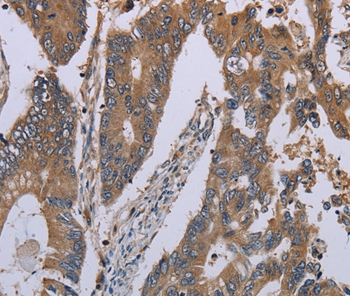

Immunohistochemical analysis of paraffin-embedded Human colon cancer tissue using #37750 at dilution 1/30.

Immunohistochemical analysis of paraffin-embedded Human liver cancer tissue using #37750 at dilution 1/30.